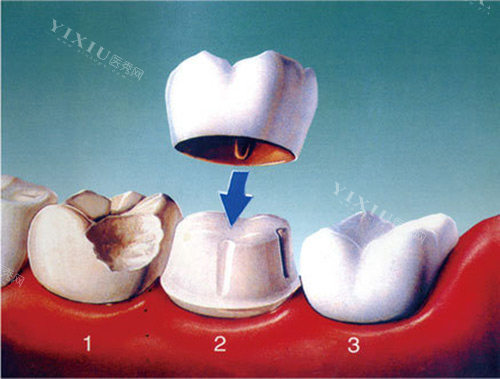

天津市北辰医院口腔科烤瓷牙全瓷牙价格表

国产爱尔创全瓷牙冠:1600 元起

镍镉烤瓷牙:1759 - 2026 元起

钛合金烤瓷牙:1580 元起

贵金属牙冠:3455 元起

碳素牙冠:1995 元起

高分子牙冠:1512 - 1885 元起

陶瓷牙冠:1518 - 3160 元起

纯钛烤瓷牙:2422 - 2617 元起

烤瓷牙连冠:1773 元起

桩顶烤瓷牙:1240 元起

烤瓷牙搭桥:1114 元起